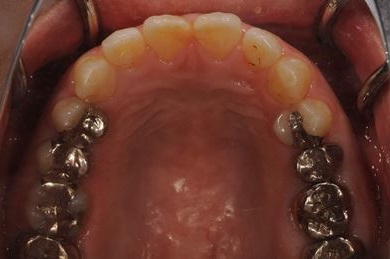

抜歯即日スピードインプラント治療+セラミック治療+歯肉歯槽骨整形術

| 治療内容 | インプラント2本(抜歯即日スピードインプラント)、ハイブリッドセラミッククラウン2本、歯肉歯槽骨整形術 | ||||||||||||||||||||||||||||||||